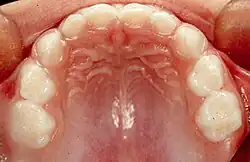

Dentición decidua

La dentición decidua, conocida también como dentición de leche, dentición temporal, dentición primaria, o dientes mamones,[1] es el primer juego de dientes que aparecen durante la ontogenia de humanos y como en las de otros mamíferos. Se desarrollan durante el periodo embrionario y se hacen visibles (erupción dentaria) en la boca durante la infancia. Son generalmente sustituidos, tras su caída, por dientes permanentes, aunque, en ausencia de ésta, pueden conservarse y mantener su función algunos años. En todos los mamíferos, salvo algunas excepciones, se recambian solo incisivos, caninos y premolares, apareciendo los molares ya como parte de la serie dentaria definitiva; este tipo de reemplazo se denomina hemifiodoncia.[2]

En la dentición temporal hay 20 dientes en total: 8 incisivos, 4 caninos y 8 molares temporales.